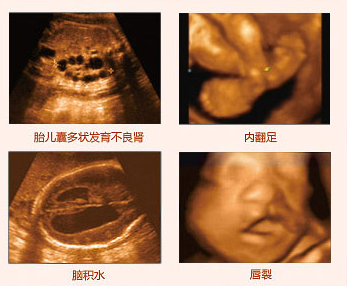

莆田盛興醫(yī)院引進(jìn)的美囯GE四維彩超,擁有當(dāng)今超聲發(fā)展較前沿的技術(shù),拓展了超聲臨床應(yīng)用范圍。美囯GE四維彩超能夠多方位、多角度地觀察宮內(nèi)胎兒的生長發(fā)育情況,為早期診斷胎兒先天性體表畸形和先天性心臟疾病提供準(zhǔn)確的科學(xué)依據(jù)。不僅能夠發(fā)現(xiàn)體表畸形,同時(shí)能夠?qū)崟r(shí)的觀察人體內(nèi)部器官的動態(tài)運(yùn)動??梢詸z測和發(fā)現(xiàn)各種異常,從血管畸形到遺傳性綜合征等。推選閱讀 四維彩超可以排查胎兒哪些畸形

四維彩超排畸圖像

一般來說妊娠10周以上都可以做四維彩超,但是為了達(dá)到檢查胎兒是否畸形的目的,懷孕24周到27周做四維彩超是較為合適的時(shí)間。若是平時(shí)產(chǎn)檢無異常胎兒沒有偏大或偏小的情況,較多可延長至28周。 胎兒24周左右時(shí)正是大腦突飛猛進(jìn)的發(fā)育時(shí)期,這個時(shí)期的胎兒結(jié)構(gòu)已經(jīng)形成,大小及羊水適中,在宮內(nèi)的活動空間較大,胎兒骨骼回聲影響比較小,圖像也比較清晰。推選閱讀 莆田孕媽都去哪里做四維彩超